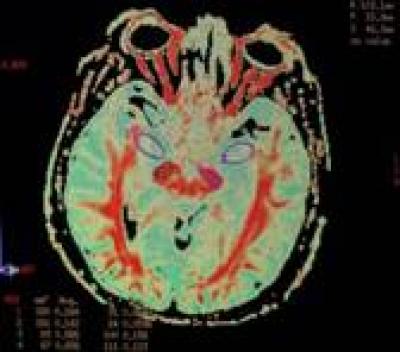

Psychosis is a common non-motor symptom of Parkinson's disease whose pathogenesis remains poorly understood. Parkinson's disease in conjunction with psychosis has been shown to induce injury to extracorticospinal tracts as well as within some cortical areas. Jingmei Zhong and colleagues from First People's Hospital of Yunnan Province, China conducted a diffusion tensor imaging study in parkinson's disease patients with psychosis who did not receive antipsychotic treatment and those without psychosis, to determine whether the degree of white-matter fiber injury in brain regions associated with psychiatric symptoms is different from that which occurs in the extrapyramidal motor system. Results revealed that damage to the white-matter fibers in the brain regions associated with psychiatric symptoms were greater than that which occurs in the extrapyramidal motor system, which might explain why psychosis often occurs in Parkinson's disease patients. Using fractional anisotropy ratios of several brain regions, diffusion tensor imaging can be used to observe the relative degree of injury in brain regions associated with mental diseases, information that is valuable in the clinic and in scientific research. These findings were published in the Neural Regeneration Research (Vol. 8, No. 27, 2013).